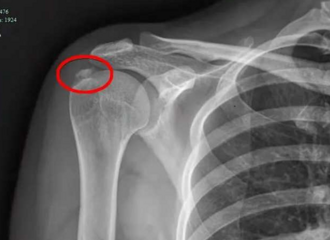

• 女子常在深夜被痛醒,抽丝破茧后,医生竟从她右肩挤出“牙膏”

女子常在深夜被痛醒,抽丝破茧后,医生竟从她右肩挤出“牙膏”